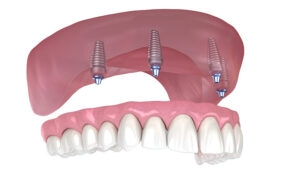

Protesi fissa su 2 - 4 impianti dentali

Innestando almeno due impianti dentali nella mascella inferiore, possiamo fissare la protesi sui localizzatori per renderla fissa. Una soluzione ideale ed economica, la consigliamo a ogni paziente affetto da edentulismo nella mascella inferiore.

Protesi fissa All on 4

Una soluzione innovativa per trasformare rapidamente la mascella edentula in un sorriso funzionale e bello esteticamente con un numero minimo di impianti.